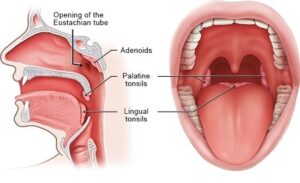

اين تقع اللوزتين؟

هما عبارة عن 2 من ال غدد الليمفاوية –

غدد الليمفاوية –

في حجم حبة اللوز عند الكبار –

تقع علي جانبي الحلق من الداخل في الجهة العلوية –